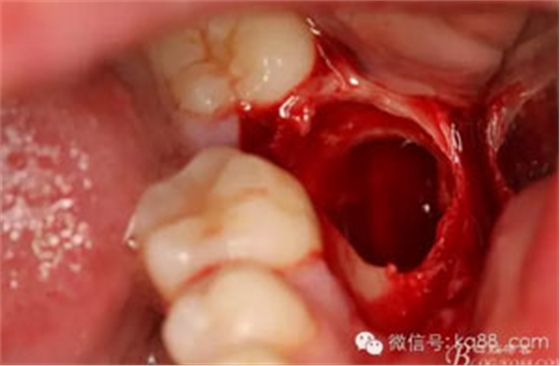

圖15.37拔除后的牙槽窩情況

15.jpg